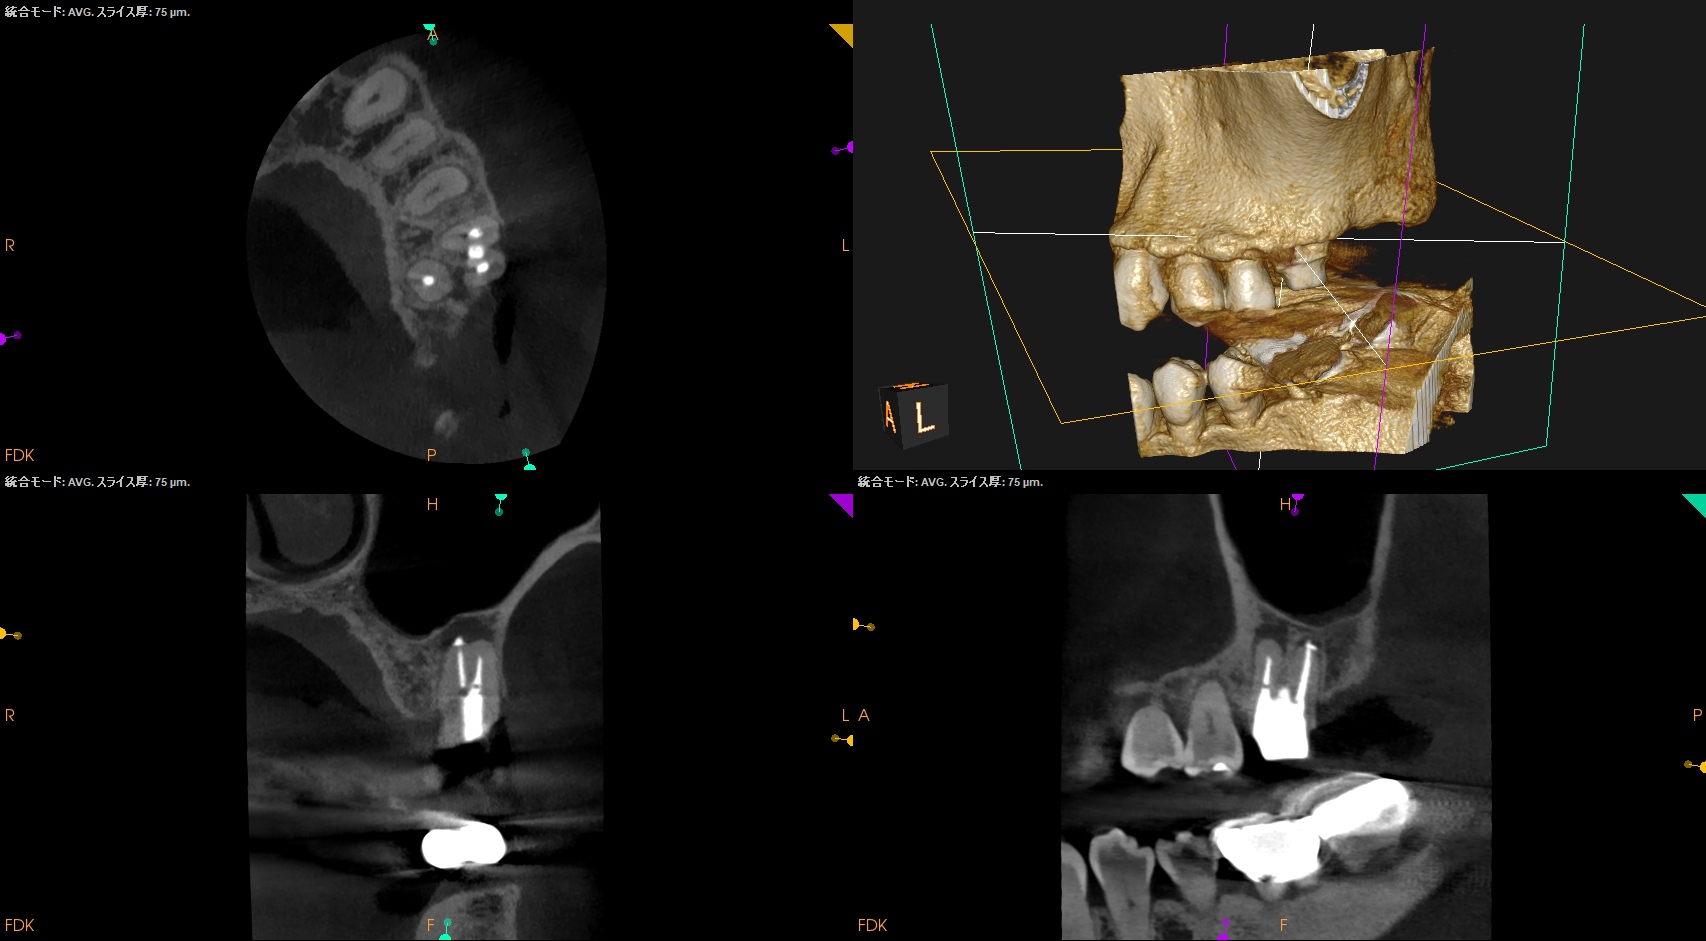

この際の切断面が上記のCBCTの絵の咬合面観に相似であるので問題がない、ということもわかるだろう。

CBCTを参考にCEJよりDBのApexを測定し該当部位をOsteotomyし、Root resectionし、メチレンブルーで染色した。

この際の断面が上記のCBCTの絵に掃除であれば問題ないが、切り残し(アゴ)が残存したので切断し直している。

術後にPA, CBCTを撮影した。

MB

DB

問題はないだろう。